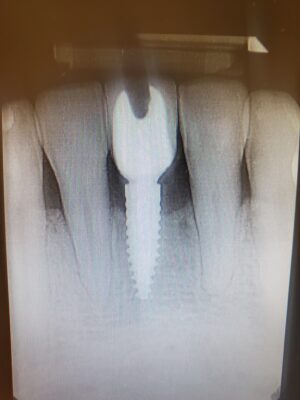

I have a patient who has a cemented implant crown but wants it changed do to color. What techniques or methods do clinicians have to help remove the crown safely? I have tried to prep into crown searching for screw but that can be fruitless. Hoping some people have pearls.

Unfortunately, no magic to this procedure. It definitely helps to go slow and I use a flat tapered diamond but or a diamond chamfer bur. Definitely, looking at multiple X-rays to have your best access location is helpful but it just takes that along with patience. Also, if it’s not your crown you may not be fortunate to find teflon, it may just…